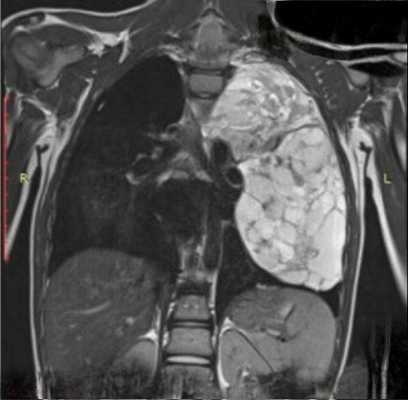

Лимфомы медиастинальной локализации не всегда диагностируются при рентгенологическом обследовании. Компьютерная томография, более детально, чем обзорная рентгенография позволяет рассмотреть конгломерат опухоли, увеличение лимфоузлов средостения, вовлечение паратрахеальных, трахеобронхиальных, прикорневых лимфатических узлов. Диагностическая значимость магнитно-резонансной томографии в верификации лимфом средостения признается не всеми авторами.

КТ ОГК. Объемное образование в средостении (патологически измененный лимфоузел), подтвержденная лимфома.